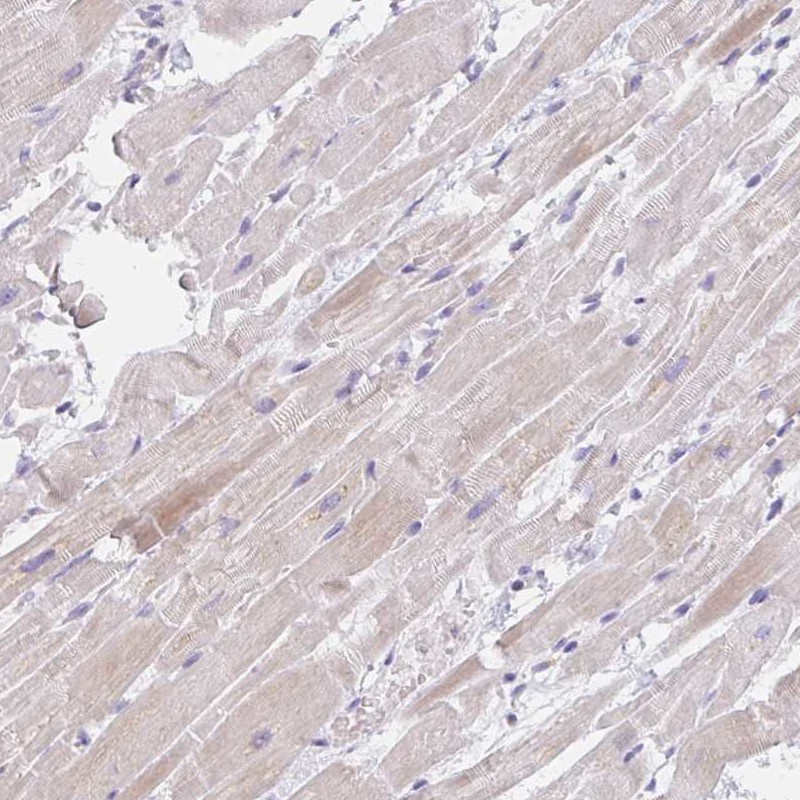

Immunohistochemistry analysis in human skeletal muscle and heart muscle tissues using Anti-CACNA1S antibody. Corresponding CACNA1S RNA-seq data are presented for the same tissues.